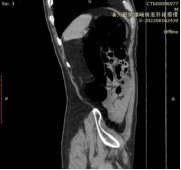

特殊断层图像:展示柔软、菲薄如纸的大肠壁;观察肠外情况。

俯卧超薄断层像

矢状位